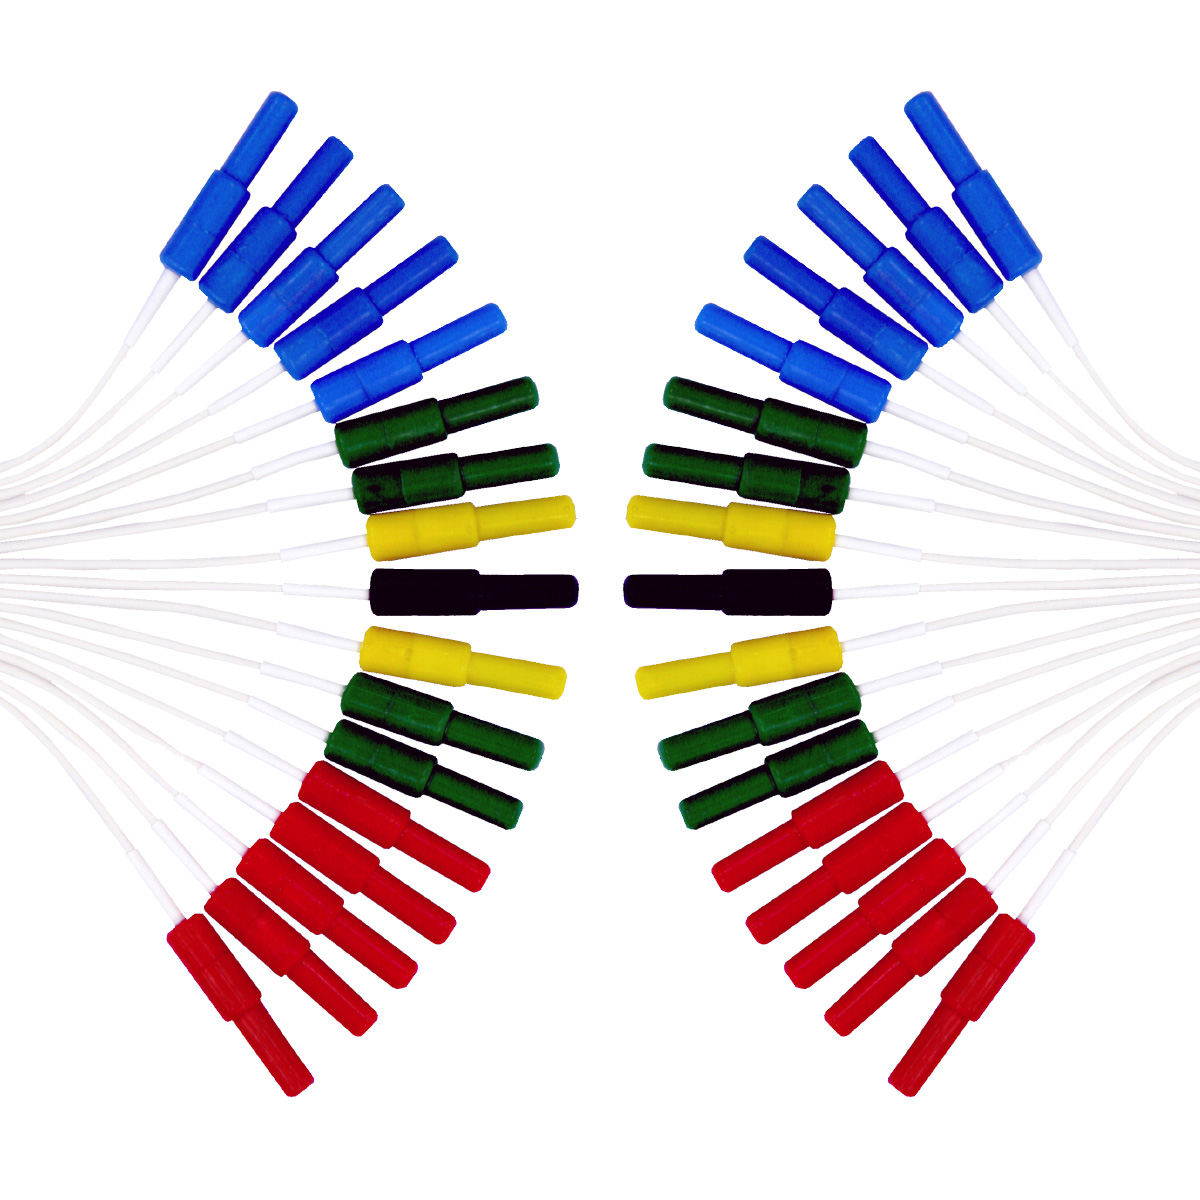

Os Eletrodos Concha de Prata são a escolha profissional para exames de EEG e PSG, combinando alta qualidade técnica e segurança. Fabricados com conector Touch Proof (pino de segurança), concha banhada a ouro e fios de Kevlar ultra-resistentes, garantem durabilidade excepcional e precisão na captação de sinais elétricos cerebrais.

– Conjunto com 25 unidades, pronto para uso em clínicas, hospitais e laboratórios.

Aplicações: Exames de EEG, polissonografia (PSG), monitoramento neurológico, pesquisa clínica e diagnóstico pediátrico.

Ideal para: Hospitais, clínicas de sono, neurologistas, técnicos em neurofisiologia e laboratórios de diagnóstico.